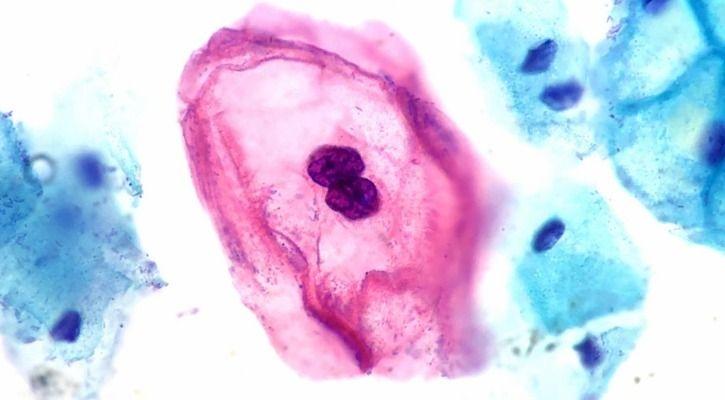

6. Cure for HPV

HPV - or Human Papillomavirus - is a very common virus strain worldwide with over 100 variants. 14 of those can cause cancer at the very least. For the past 20 years, no cure was found until just recently a 100% cure for the virus was found with zero side effects.